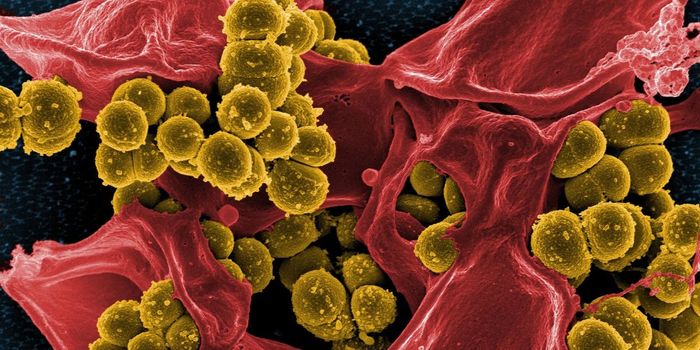

SEP 17, 2021Cell & Molecular BiologyMRSA (methicillin-resistant Staphylococcus aureus) is a well known superbug, a pathogenic microbe that can cause serious ...